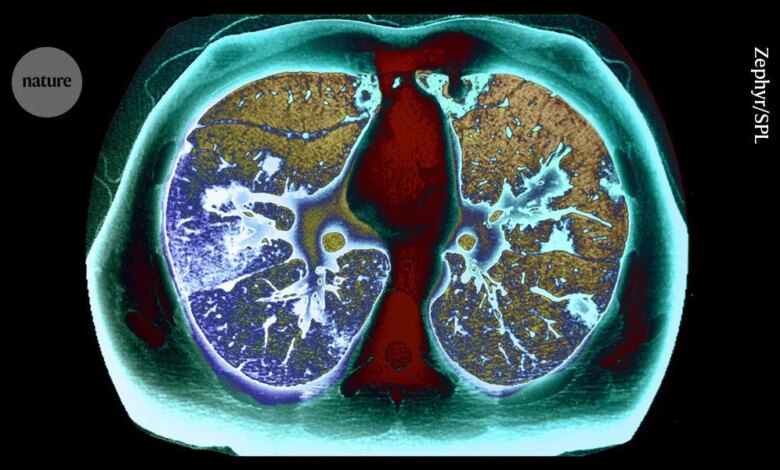

يقوم برنامج يقدم فحوصات للمدخنين الذين تتراوح أعمارهم بين 55 و74 عامًا بالكشف عن عدد كبير من أورام الرئة في المراحل المبكرة.